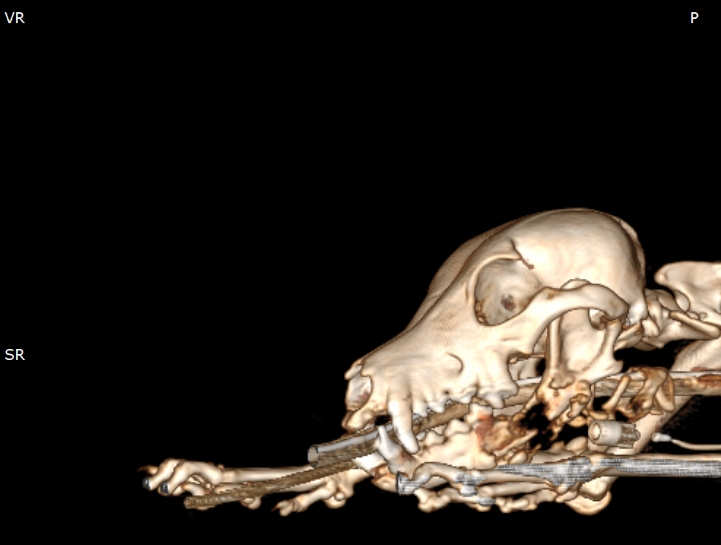

狗狗電腦斷層掃描 不明原因口腔出血 嚴重牙周病 口腔惡性腫瘤 鱗狀上皮細胞癌(Squamous cell carcinoma,SCC)

主訴嘴巴突然流血 口腔潰爛 左下顎腫脹 同時有嚴重牙周病 經由口腔採樣 電腦斷層掃描 確認為鱗狀上皮細胞癌(Squamous cell carcinoma,SCC)同時已經侵犯下顎骨。

確診後經由外科醫師、腫瘤科醫師、電腦斷層影像科醫師共同擬定治療計畫後

,大範圍切除左下顎,經過一年追蹤,目前狗狗一切安好喔。